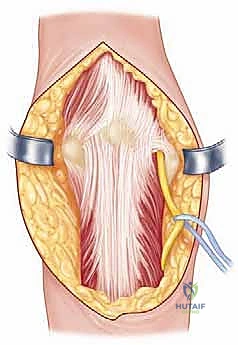

Definitive osteosynthesis is achieved through the application of dual pre-contoured anatomical plates. Following the principles of parallel plating, a plate is applied to the medial ridge and another to the lateral ridge of the distal humerus. The plates are positioned to maximize screw purchase in the distal articular block; ideally, multiple screws should interdigitate through the articular fragments, creating a "rebar" effect. The plates must be compressed to the bone using standard lag techniques or articulated tension devices before deploying locking screws. The stability of the construct is then rigorously tested by taking the elbow through a full, unhindered range of motion. Finally, the olecranon osteotomy is meticulously repaired using the previously drilled lag screw supplemented with a figure-of-eight tension band wire, or via a dedicated proximal ulna locking plate, ensuring rigid fixation to allow for immediate postoperative rehabilitation.